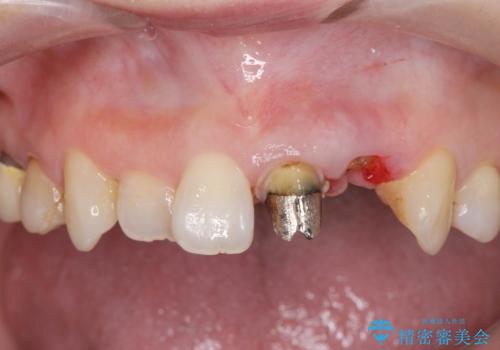

- 前歯がクラグラして噛めないことの改善を求めて来院されました。

X線撮影や歯周組織検査から、クラウン下の虫歯の再発や歯の破折が疑われる状況でした。

左上2は、クラウン メタルコアの除去を行ったところ虫歯の再発や亀裂を認め、長期的な予後の期待が難しいことから抜歯を行い

ブリッジで審美性の回復を行っていく運びとなりました。